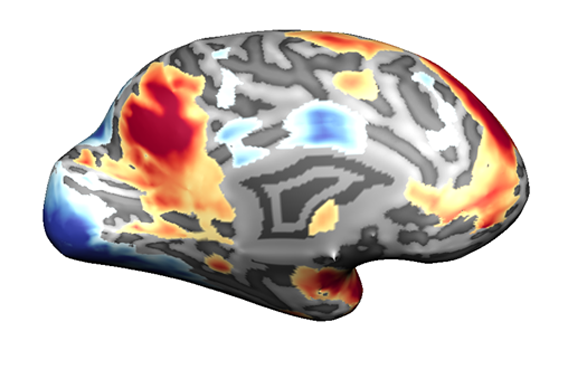

עבור כל ווקסל נרצה לבחון אם היה שינוי באות בזמן ביצוע המטלה, לעומת רמת האות שנמדדה בתנאי הביקורת. מוח ועליו מסומנים ווקסלים שמעלים את פעילותם (בגוונים חמים) ואלו שמורידים את פעילותם (בגוונים קרים) כאשר נבדקים הזדהו עם רגשות של אחרים | התמונה באדיבות ד”ר עדי יניב